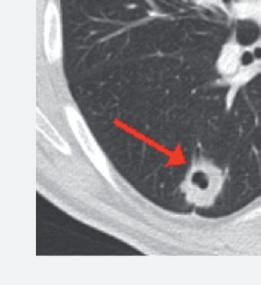

Anche la necrosi del tumore può essere considerata un marcatore predittivo di beneficio clinico. Cambiamenti della densità tumorale ed anche necrosi di lesioni polmonari sono state descritte in pazienti che ricevevano terapia antiangiogenica e vengono considerate come risposta della malattia. L’analisi post-hoc dello studio CORRECT (RadioCORRECT)14 ha mostrato che una precoce valutazione radiologica a 8 settimane è utile per predire i risultati clinici della terapia con regorafenib nei pazienti con metastasi polmonari al basale. Il 20% dei pazienti con metastasi polmonari nel braccio con regorafenib presentavano cavitazione alla CECT basale. Questi pazienti erano quelli che più verosimilmente

Figura 7. Correlazione tra HFSR e sopravvivenza nello studio osservazionale post-marketing giapponese13

hanno sviluppato un aumento della cavitazione a 8 settimane e hanno raggiunto una maggiore PFS e OS rispetto ai pazienti che non presentavano cavitazione al basale.

Figura 8. RadioCORRECT: esempio di cavitazione polmonare a 8 settimane14

Prima del trattamento con regorafenib.

Dopo il trattamento con regorafenib.